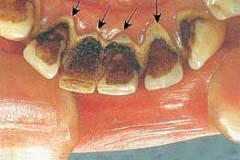

以齦緣為界,根據牙石沉積的部位,分為齦上牙石和齦下牙石。

齦上牙石,又稱唾石,是位於齦緣以上臨床牙冠表面上的牙石,肉眼可以直接看見。其礦化物質來源於唾液,因此在唾液腺導管開口處相應處的牙面上常常沉積較多,即在腮腺導管開口處相應的上頜第一磨牙頰面,頜下腺和舌下腺導管開口處相應的下頜前牙舌面容易沉積牙石。齦上牙石多呈黃色或白色,也可以由於吸菸或食物著色而呈深色。

齦下牙石又稱為血石,沉積於齦緣之下,附著在齦溝或牙周袋內的根面,肉眼不可以直接看見,大塊齦下牙石可以在X線片上顯示。其礦化物質來源於齦溝液,一般呈褐色或黑色,與牙面的附著較齦上牙石更牢固。